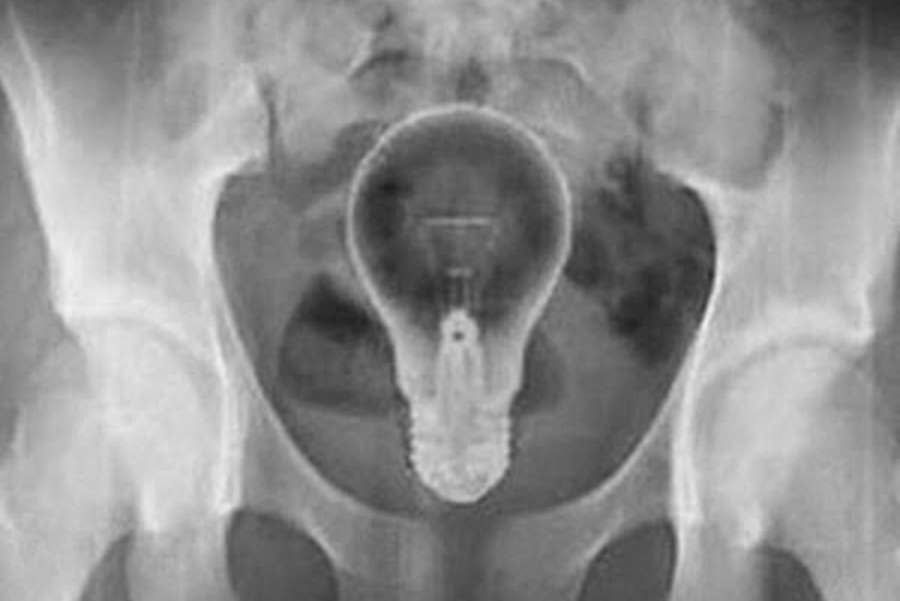

Foragido é preso com lâmpada no @nus, após pedir socorro da PRF

O homem de 45 anos sentia fortes dores. Ele foi socorrido às pressas ao hospital João Paulo II